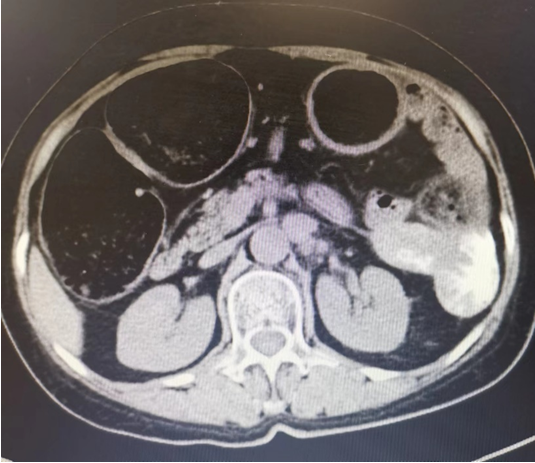

患者原先手术为开放手术,腹部正中可见陈旧手术切口长约16cm,腹部膨隆,未及压痛及反跳痛。腹部CT提示左上腹较大病灶(6.6*4.5cm)累及降结肠至相应管腔狭窄,结肠梗阻,肝S7血管瘤,其余肝脏未见异常(图1)。

图片

图片图1